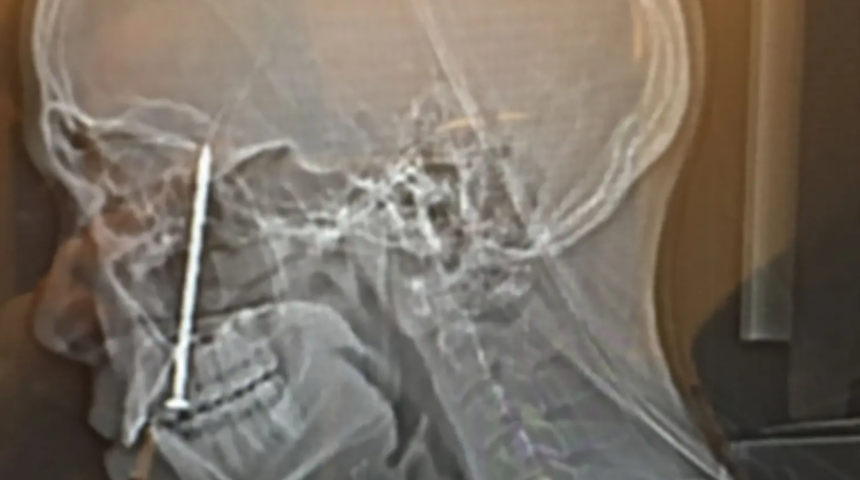

Korkunç kaza! Elektrikli çivi makinesi bir anda patladı... Diline ve kafatasına çiviler saplandı

Kaliforniyalı bir marangoz çırağı, bir inşaat sahasında elektrikli bir aletin patlayarak diline ve kafatasına çivilerin saplanmasına neden olması sonucu korkunç bir şekilde yaralandı. Olayın ardından iyileşme sürecinin başladığı 28 yaşındaki Timothy Kualii Kahae cihazın kusurlu olduğunu iddia ederek firmayı mahkemeye verdi.

Amerika Birleşik Devletleri'nin Kaliforniya eyaletinde yaşayan 28 yaşındaki Timothy Kualii Kahae isimli genç bir adam 15 Kasım 2021'de Körfez Bölgesi'nde elektronik çivi makinesinin bir anda patlaması sonucunda feci şekilde yaralandı. Sacramento Bee'nin haberine göre, patlayan cihazdan iki çivi dışarı çıktı. 3 Kasım'da federal mahkemeye sunulan şikayete göre çivilerden biri diğerine çarptı ve dilinin içinden kafatasının içine doğru yol aldı.

Dava dilekçesinde yer alan ifadelere göre, marangoz çırağı Timothy Kualii Kahae'in şoka girdiği ve acilen hastaneye kaldırıldığı ifade edildi. Hastanede çivilerin çıkartılması için ameliyat olan Kahae ayrıca dilini, damağını, burun septumunu, sinüslerini, kafatasını ve kırık çenesini onarmak için çok sayıda ameliyat geçirdi.

Davada, "Timothy'nin dilinde çivinin girdiği yerde uyuşukluk hissetmeye devam ettiği ve bunun da kekemeliğe yol açtığı ve alt dudağında kalıcı bir yara izi olduğu " iddia ediliyor. Şikayete göre, olay sonucunda 400.000 dolardan (yaklaşık 11 milyon 421 TL) fazla sağlık faturası toplandı ve 30.000 (yaklaşık 856 bin TL) dolardan fazla maaş kaybı yaşandı. Kahae iyileşme sürecinin devam ettiğini söylerken elektronik çivi makinesinin şirketine tazminat davası açtığını belirtti.